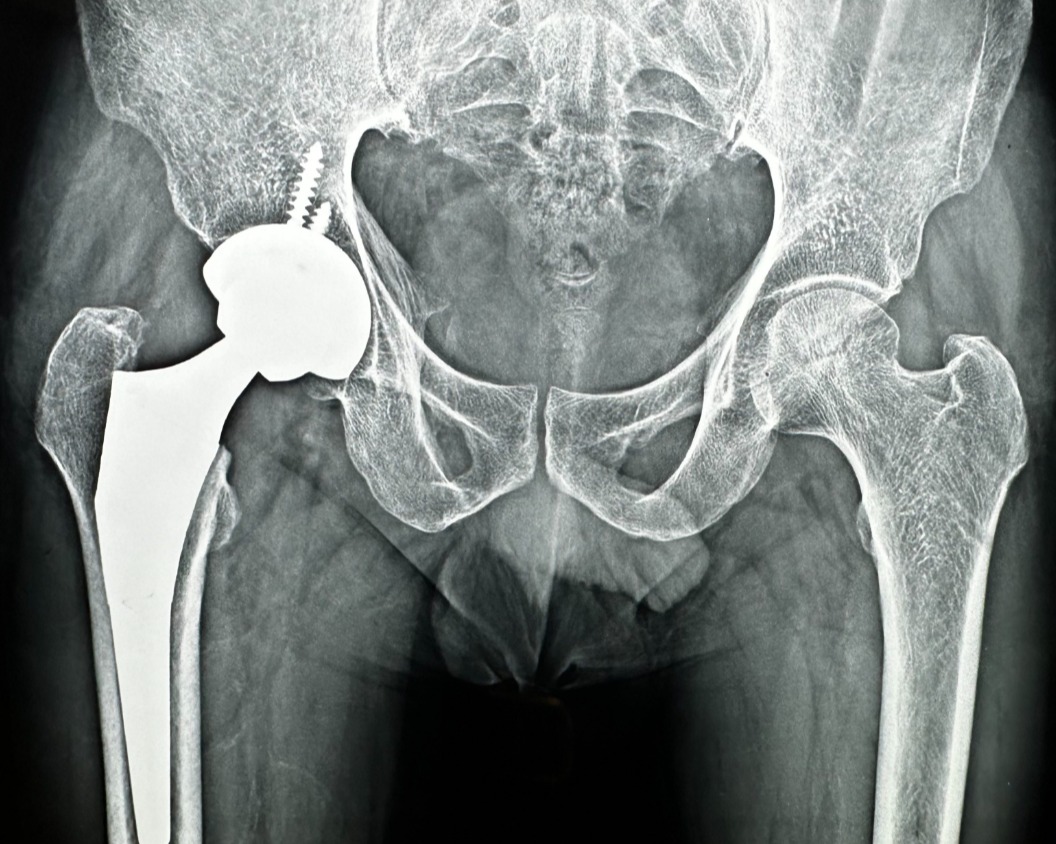

Living with constant hip pain can gradually take away the joy of simple moments like walking, climbing stairs, or sitting comfortably. If conservative treatments no longer help, hip replacement could be the most effective step toward long-term relief. At Phoenix Orthopedic Superspecialty Hospital in Nagpur, experienced orthopedic specialists combine precision techniques with advanced implants to restore natural hip movement and stability.

This procedure involves replacing the damaged hip joint with a durable artificial implant designed to mimic natural motion. The focus is not just on eliminating pain but on helping patients regain flexibility, balance, and confidence. Proper post-surgery rehabilitation further ensures a smooth transition to an active lifestyle.